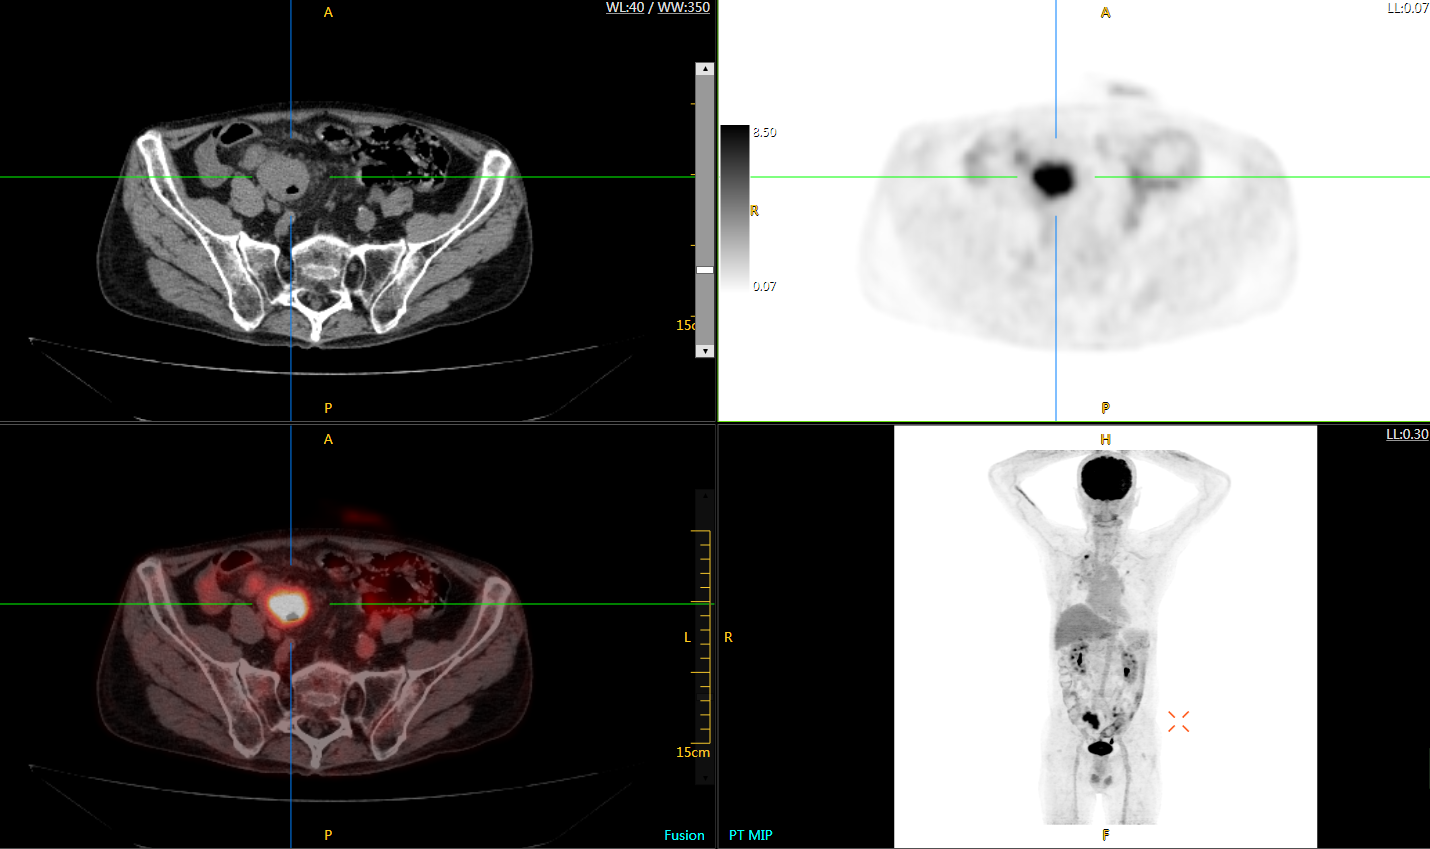

肺癌轉(zhuǎn)移及復(fù)發(fā)

患者男性,66歲,七年前發(fā)現(xiàn)右肺肺癌,其間手術(shù)兩次,共切除兩個(gè)肺葉,復(fù)查;

診斷意見,回腸轉(zhuǎn)移,右肺殘留部復(fù)發(fā)